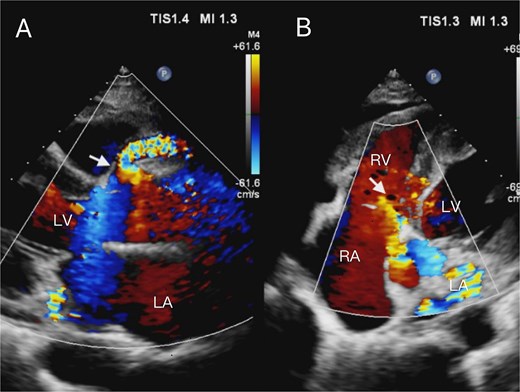

A 52-year-old woman presented to our hospital with a 2-week history of idiopathic chest tightness and chest pain. Physical examination showed systolic hypertension (140/73 mmHg). The patient had no personal or family history of cardiovascular risk factors, such as hypertension, hyperlipidemia, or diabetes mellitus. The electrocardiogram obtained at admission showed a heart rate of 80 beats per minute, normal sinus rhythm, and T-wave abnormalities. Initial laboratory evaluation revealed elevated B-type natriuretic peptide levels, while serum troponin T remained within normal limits. Routine transthoracic echocardiography revealed aneurysmal coronary artery dilation with abnormal flow trajectory (Fig. 1). Parasternal long-axis views demonstrated aneurysmal dilation of the right coronary sinus and proximal right coronary artery (Fig. 1A). Subsequent apical five-chamber views identified a fistulous orifice in the right coronary artery draining superior to the tricuspid septal leaflet into the right atrium (Fig. 1B), with a measured orifice diameter of ~5.8 mm. Subsequent coronary computed tomography angiography (CCTA) with three-dimensional reconstruction confirmed our echocardiographic findings, revealing extensive aneurysmal dilation of the right coronary artery with an RCA – RA fistula (Fig. 2A–D, Supplementary Video 1). Selective coronary angiography was performed during hospitalization, which further confirmed the presence of a giant right coronary artery aneurysm (Fig. 2E and F, Supplementary Video 2) and revealed no significant stenosis or pathology in the left coronary system. Furthermore, cardiac catheterization quantified a pulmonary-to-systemic flow ratio (Qp:Qs) of 1.8:1, indicating a moderate left-to-right shunt. Based on these findings, the patient was diagnosed with a right CAF and a giant right coronary artery aneurysm.

Enhanced CT coronary angiography confirmed the presence of a right coronary artery to right atrium fistula with a giant right coronary artery (A, B, arrows). Three-dimensional reconstruction (C, D, arrows) and selective coronary angiography further confirmed these findings (E, F, arrows). Intraoperative photograph clearly showing the giant right coronary artery (G, arrow), and the patient subsequently underwent fistula ligation under cardiopulmonary bypass (H, arrow).

Given the patient’s significant chest discomfort and pain, along with clear surgical indications and no contraindications, fistula ligation was performed via median sternotomy on cardiopulmonary bypass. Following cannulation of the aorta, superior vena cava, and inferior vena cava, the lines were de-aired and connected to the cardiopulmonary bypass circuit. The patient was systemically cooled to a nasopharyngeal temperature of 32°C. Given the significant coronary steal phenomenon, meticulous myocardial protection was paramount. Our strategy consisted of antegrade cold blood cardioplegia administered via the aortic root, supplemented by topical cardiac cooling with ice-slush saline. Particular attention was paid to the infusion pressure and volume of the cardioplegic solution due to the potential for altered distribution caused by the fistula. Complete electromechanical arrest of the heart was subsequently confirmed. During the procedure, a right atriotomy was performed and the coronary sinus orifice was enlarged, but no distinct fistula was identified. Attempts to locate it by administering antegrade cardioplegia via the aortic root yielded no visible reflux. Consequently, the coronary artery aneurysm in the proximal posterior atrioventricular groove was incised, revealing the fistula (~6 mm in diameter) within the aneurysm lumen. The fistula was then repaired using 5-0 pledgeted sutures in an interrupted followed by a continuous fashion (Fig. 2G and H). After verifying fistula closure and performing coronary aneurysmorrhaphy, the right atriotomy was repaired using 4-0 polypropylene. The caval snares were released, the heart was de-aired, and the aortic cross-clamp was removed, resulting in the spontaneous return of sinus rhythm. The total aortic cross-clamp time was 55 min. The patient was rewarmed to 36.8°C. Cardiopulmonary bypass was discontinued after 67 min of total support, the cannulas were removed, and meticulous hemostasis was achieved.